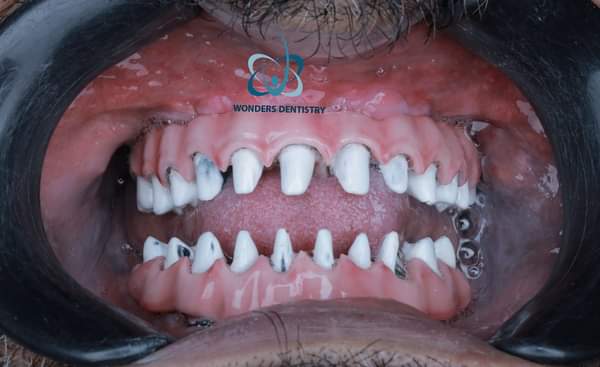

هناك فترة شفاء، عادة ما تكون بضعة أشهر (من 3 الى 6 أشهر)، مما يسمح للزرعات بالاندماج مع عظامك (الاندماج العظمي). خلال هذا الوقت، قد يتم توفير تركيبة صناعية مؤقتة للحفاظ على ابتسامة المريض و وظيفة المضغ البسيطة جدا و يتم تركيبها بعد العملية بأيام الى ان يهدأ الفك و اللثة من العملية الجراحية.

يتم أخذ طبعة من الفك ، ليتم تصميم وصنع التركيبات الصناعية النهائية بدقة، مما يضمن مظهرا طبيعيا و ملاءمة مريحة متوافقة 100% مع المريض.

يمكن أن تدعم زراعة الزيجوما أن يحصل المريض على تركيبة مؤقتة يقوم بوضعها في الفم بعد العملية بأيام و ذلك لاستعادة المظهر الجمالي الى حين الحصول على التركيبات النهائية